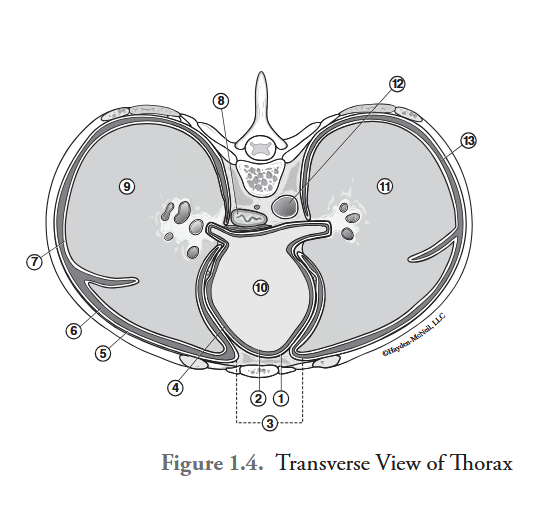

What is labeled #1?

parietal pericardium

What is labeled #2?

visceral pericardium (epicardium)

What is labeled #3?

mediastinum

What is labeled #4?

pericardial cavity

What is labeled #5?

parietal pleura

What is labeled #6?

right pleural cavity

What is labeled #7?

visceral pleura

What is labeled #8?

esophagus

What is labeled #9?

right lung

What is labeled #10?

heart

What is labeled #11?

left lung

What is labeled #12?

descending aorta

What is labeled #13?

left pleural cavity